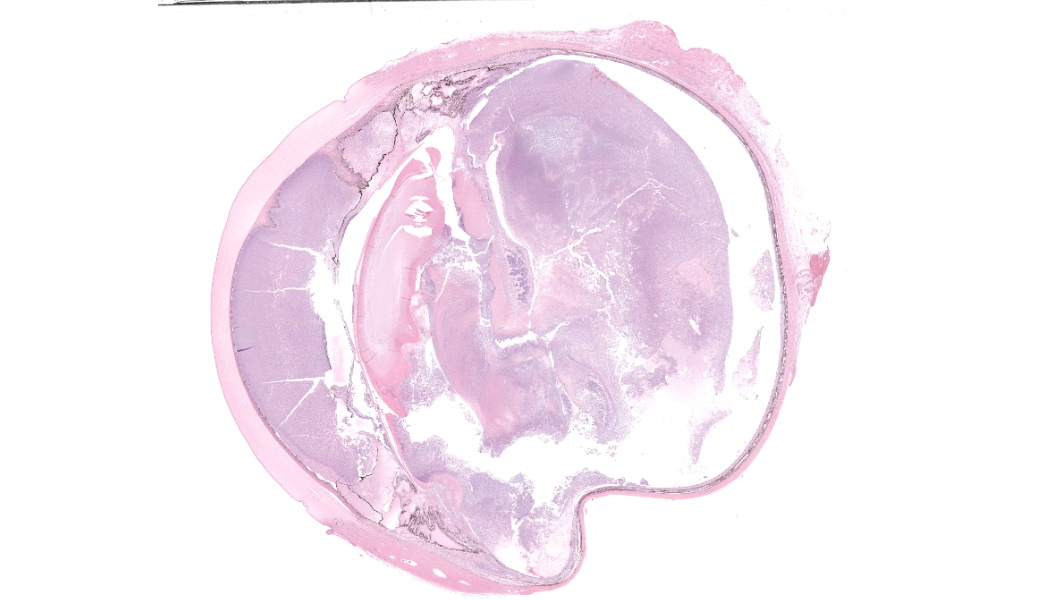

Submitted fixed in 10% neutral buffered formalin for evaluation is an enucleated eye (diameter: 31mm; cornea diameter: 18mm; axial length: 22mm) with a less than 1mm segment of optic nerve. On section of the eye, the ocular chambers contain abundant amounts of thick off-white purulent material.Laboratory Results:

Filling all ocular chambers and coating the surfaces of intraocular structures are vast accumulations of exudate consisting of myriad degenerate and intact neutrophils, many macrophages, abundant amounts of fibrinous to proteinic material, abundant necrotic cellular debris, occasional pools of extravasated erythrocytes, and multifocal colonies of mixed bacteria (rods and coccobacilli). Centrally incorporated into the inflammatory exudates is a ruptured lens which lacks a capsule in many areas and has highly undulating free capsule margins regionally. The lenticular stroma is variably vacuolated with the following features: streaks of pallor, Morgagnian globules, many infiltrating leukocytes (mostly neutrophils), and occasional pockets of similar bacteria. The retina is diffusely detached and largely inapparent apart from remnant segments of atrophied and degenerate retina enmeshed within the exudate. Suppurative to pyogranulomatous inflammatory infiltrates multifocally extend into the iris, ciliary body, choroid, optic nerve which is significantly gliotic with rarefied neuropil, and optic nerve meninges. The iris is displaced anteriorly and multifocally abuts the posterior aspect of the cornea. The anterior chamber is severely narrow, and the drainage angle is collapsed and inapparent. The corneal stroma is moderately to markedly oedematous and contains small to moderate numbers of scattered neutrophils. The anterior corneal epithelium appears attenuated in areas. The sclera is variably thinned with multifocal often perivascular infiltrates of lymphocytes and plasma cells with variable numbers of admixed neutrophils and occasional macrophages. There are increased numbers of perilimbal pigmented cells. A thin to moderately thick layer of oedematous and inflamed granulation tissue regionally lines the mid and posterior scleral margins outside the globe and extends into a bundle of periocular skeletal muscle. In addition to infiltrates of the aforementioned inflammatory cells, the granulation tissue also contains many golden-brown pigmented macrophages (siderophages) which are concentrated at the level of the ciliary body. There is abundant haemorrhage in the retrobulbar loose connective tissue.Contributor's Morphologic Diagnoses:

Endophthalmitis, diffuse, suppurative to pyogranulomatous, severe, with lens rupture, retinal detachment and degeneration/atrophy with intraocular exudation and intralesional mixed bacteria, drainage angle collapse, keratitis, corneal oedema, scleritis and regional periscleral fibrosisContributor's Comment:

Globe: Endophthalmitis, fibrinosuppurative, subacute, diffuse, severe, with lens rupture, synechiae, fibrovascular membranes, retinal detachment and atrophy, and bacterial colonies.JPC Comment: